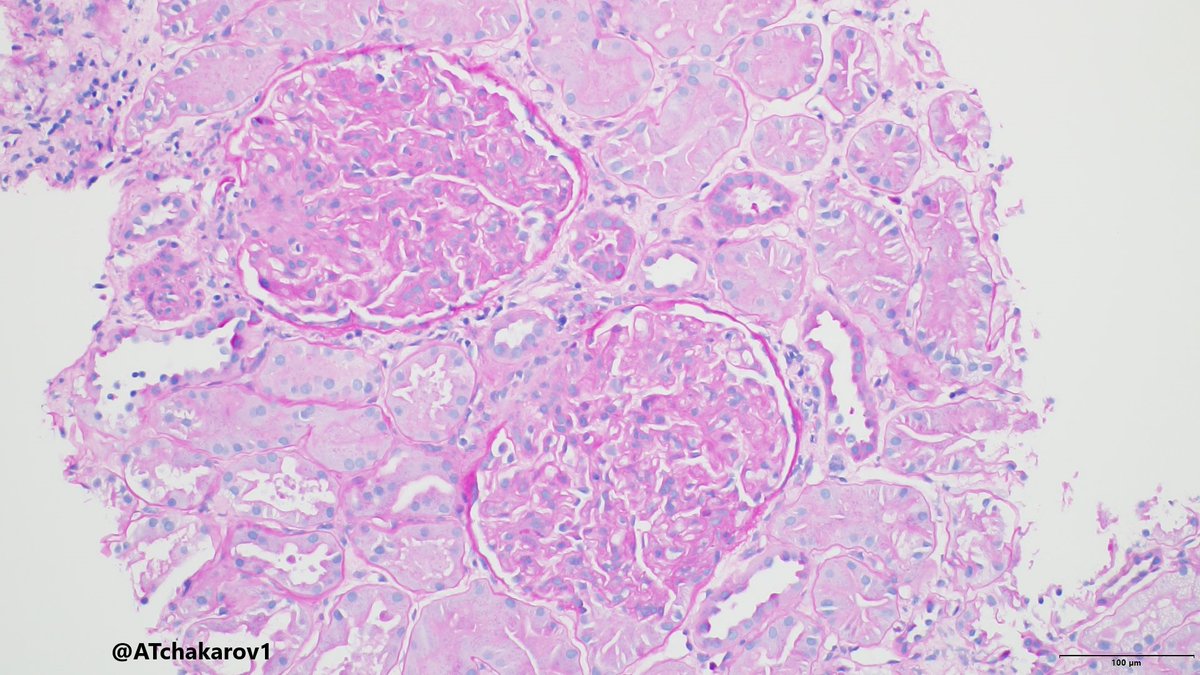

Crazy Cryo: 63 yo M w/ DM, syphilis, untreated (severe) HCV infection, bx/ed for proteinuria. Positive cryo's, SPEP with IgM-kappa paraprotein. Gloms with nodules, GBM double contours, macrophages, and intracapillary cryo aggregates. Classic EM findings. Yup, it STILL happens!

Classic example! Thanks, @JeanHouMD